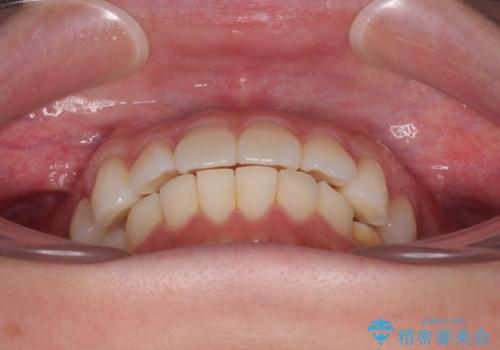

- 上下前歯の叢生を気にして来院された患者様です。

軽度な叢生であり、安価で短期間の治療を規模されていたため、インビザライン・モデレートを用いて矯正治療を行うこととしました。